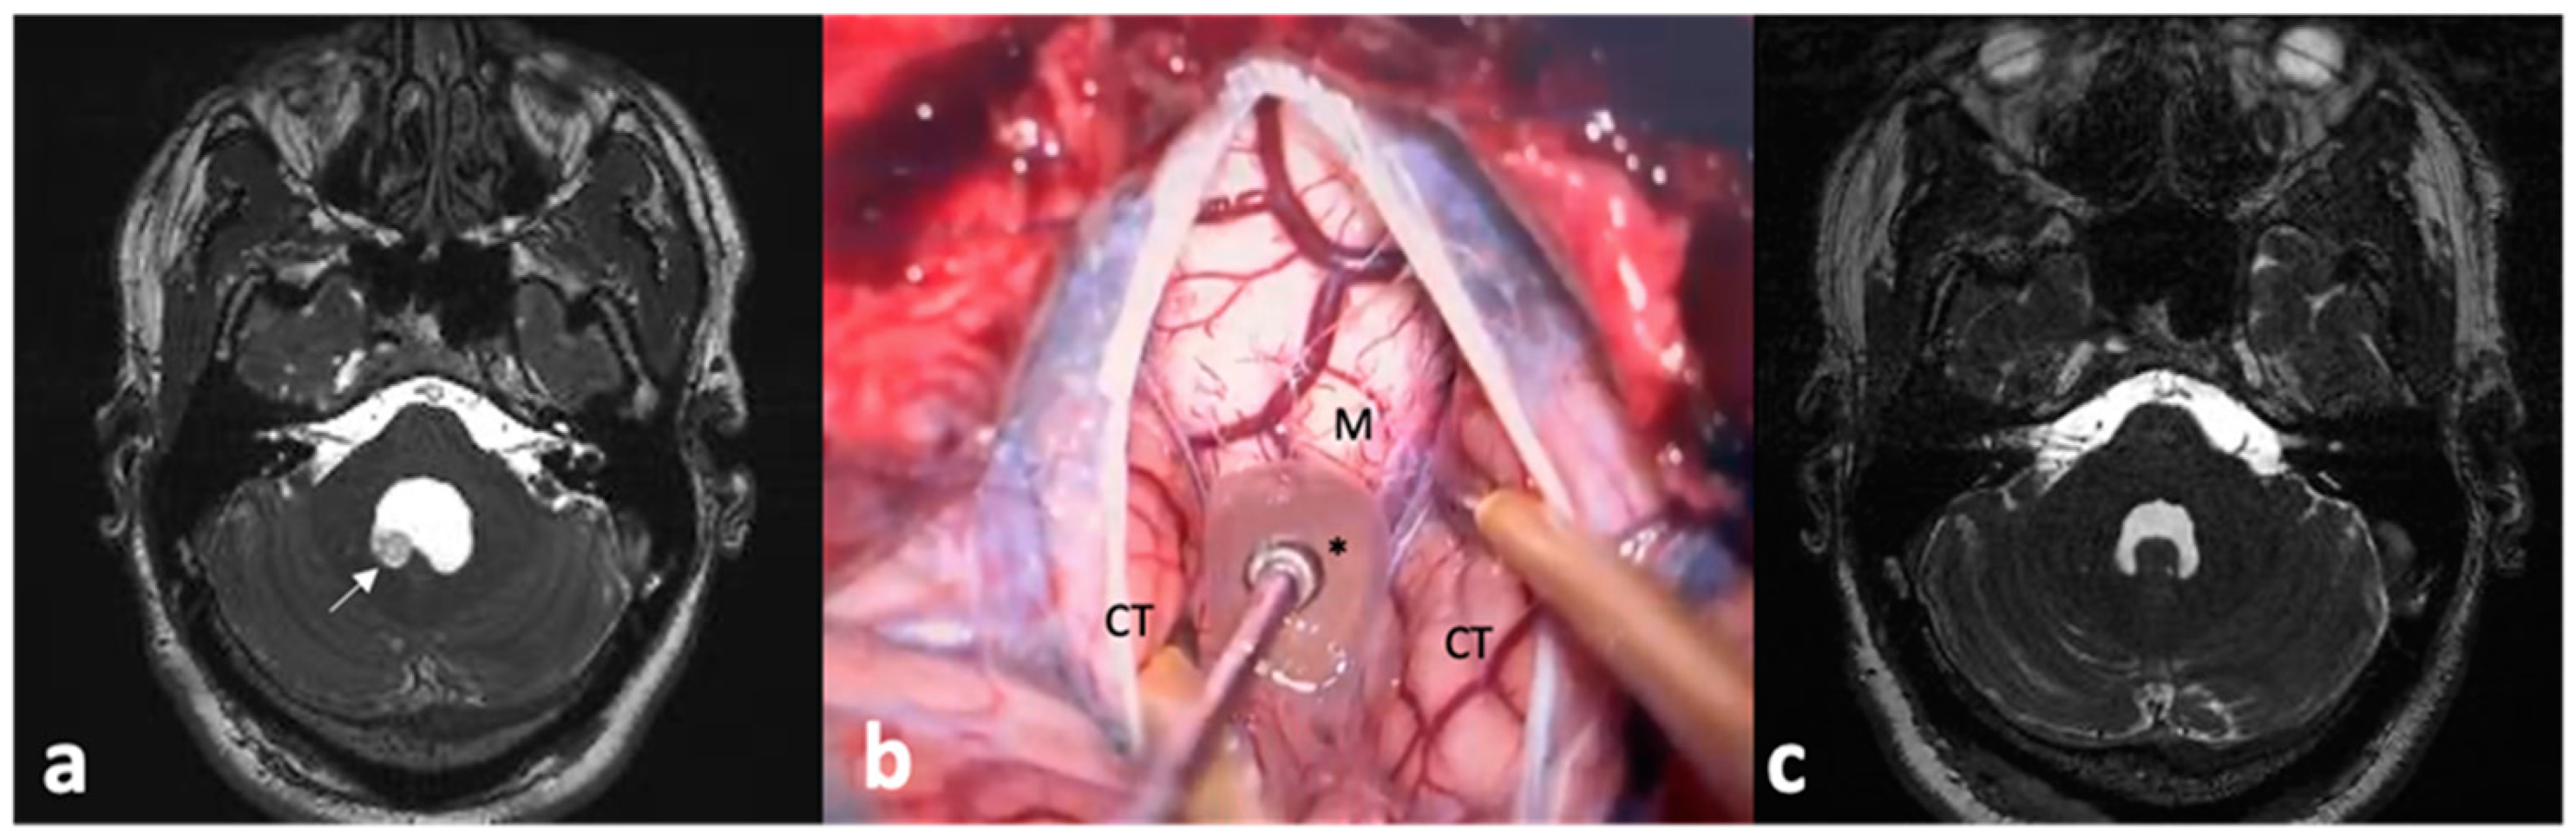

- Lines-Aguilar, W.W.; García, H.H.; Medina, J.E.; Saavedra, L.J.; Vela, E.; Lozano, M.; Vargas, J.; Cuya, C.; Heredia, D.; Apaza-Tintaya, A.; et al. Multimodal Minimally Invasive Surgery in the Treatment of Neurocysticercosis. Interdiscip. Neurosurg. Adv. Tech. Case Manag. 2024, 36, 101872. [Google Scholar] [CrossRef]

- Paiva, A.L.C.; Araujo, J.L.V.; Ferraz, V.R.; Lovato, R.M.; Pedrozo, C.A.G.; Aguiar, G.B.; Veiga, J.C.E. Surgical Treatment of Neurocysticercosis. Retrospective Cohort Study and an Illustrative Case Report. Sao Paulo Med. J. 2017, 135, 146–149. [Google Scholar] [CrossRef] [PubMed]

- Gravori, T.; Steineke, T.; Bergsneider, M. Endoscopic Removal of Cisternal Neurocysticercal Cysts. Technical Note. Technical note. Neurosurg. Focus 2002, 12, e7. [Google Scholar] [CrossRef] [PubMed]

- Rangel-Castilla, L.; Serpa, J.A.; Gopinath, S.P.; Graviss, E.A.; Diaz-Marchan, P.; White, A.C., Jr. Contemporary Neurosurgical Approaches to Neurocysticercosis. Am. J. Trop. Med. Hyg. 2009, 80, 373–378. [Google Scholar] [CrossRef]

- Rajshekhar, V. Surgical Management of Neurocysticercosis. Int. J. Surg. 2010, 8, 100–104. [Google Scholar] [CrossRef] [PubMed]